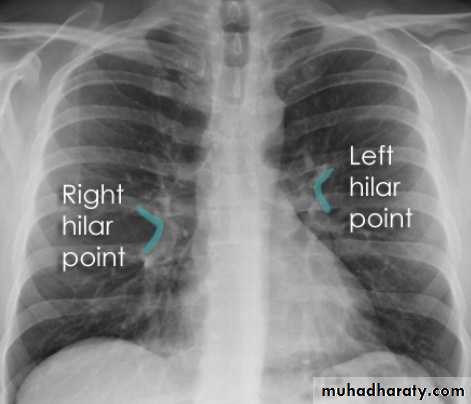

Chest imagingHilar structuresThe hila (lung roots) are complicated structures mainly consisting of the major bronchi and the pulmonary veins and arteries. These structures pass through the narrow hila on each side and then branch as they widen out into the lungs. The hila are not symmetrical but contain the same basic structures on each side.

Each hilum contains major bronchi and pulmonary vessels

There are also lymph nodes on each side(not visible unless abnormal)

The left hilum is often higher than the right

Both hila should be of similar size and density. If either hilum is bigger and more dense, this is a good indication that there is an abnormality.